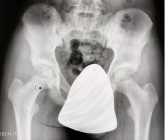

La ubicación de los protectores en los pacientes puede ser:

- Protector fuera del campo de imagen, puede ser el caso de en una RX de Tórax poner un protector gonadal.

En el caso de órganos fuera del haz directo, hay que tener en cuenta que la mayor parte de la radiación recibida provienen del interior de del organismo y el uso de protección externa no impide la llegada de esta radiación.

- Protector dentro del campo de imagen, como el caso de protector de cristalino para un TAC de cráneo.

El uso de prendas de protección no es una forma eficaz de reducir la dosis de radiación y puede impedir obtener una buena imagen ya que Si no está bien colocado puede ocultar patologías.